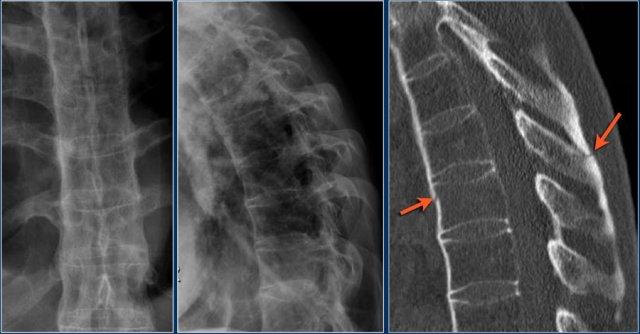

Cột sống cứng

Bệnh nhân có cột sống cứng (như trong viêm cột sống dính khớp, DISH và viêm khớp dạng thấp) dễ bị gãy xương cột sống hơn, ngay cả sau chấn thương nhẹ (6).

Vôi hóa dây chằng cột sống và vôi hóa vòng sợi đĩa đệm làm thay đổi cơ sinh học của cột sống, tạo ra các cánh tay đòn dài và hạn chế khả năng hấp thụ ngay cả những va chạm nhỏ.

Xương thường rất loãng.

Các hình ảnh là của một bệnh nhân với hình ảnh cột sống tre điển hình do viêm cột sống dính khớp.

Sau khi ngã ngửa, không thấy gãy xương trên phim X-quang.

Tuy nhiên, CT cho thấy một đường gãy mảnh qua mặt trước thân đốt sống và cả qua mỏm gai.